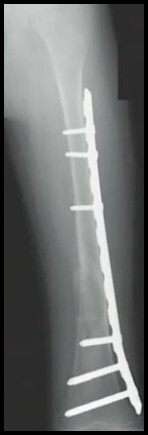

11

Q

FX Diafisária do Fêmur

Detalhe Placa Submuscular (3)

A

1. Ideal em padrões cominuídos e pouco estáveis

2. Técnica em PONTE

3. Evitar bloqueio na ponte